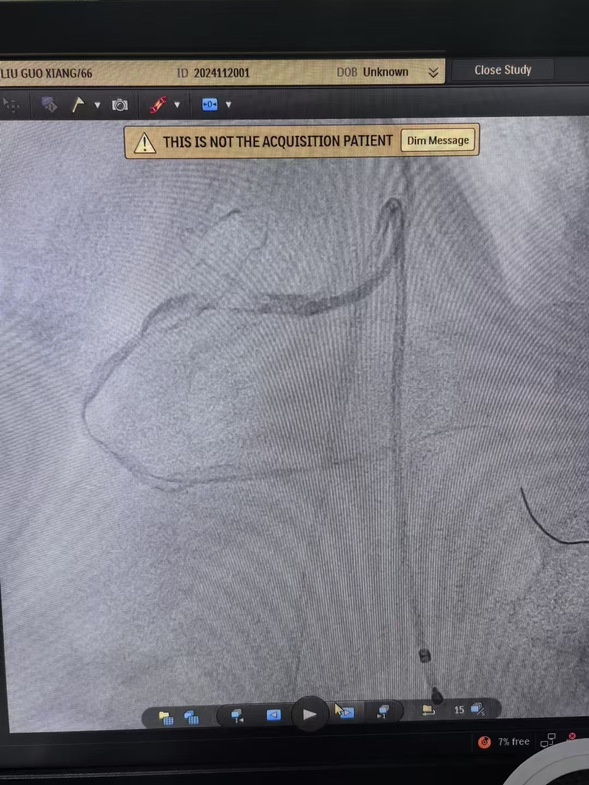

早7点,患者经120迅速到达我院大门,此时患者面色苍白、出汗明显、疼痛难止。我院医务人员立即通过绿色通道绕行急诊和病房,以最快速度将患者转移到介入手术室。在规范执行胸痛中心双绕流程基础上,心血管内四科主任沈彦祥带领医生孙智睿经临时起搏、血栓抽吸,患者胸痛症状得以缓解,状态良好。

术前、术中、术后影像